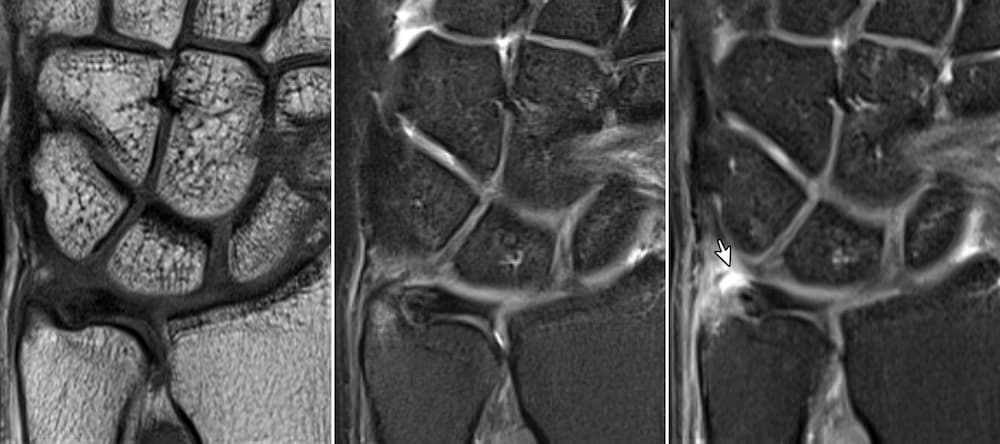

Απεικονιστικός Έλεγχος

- MRI καρπού: βασική εξέταση

- MR arthrogram: αυξημένη ακρίβεια σε επιλεγμένες περιπτώσεις

Wrist Arthroscopy

- θεωρείται gold standard

- επιτρέπει ταυτόχρονα διάγνωση και θεραπεία

Η αρθροσκόπηση καρπού αποτελεί το πιο αξιόπιστο διαγνωστικό εργαλείο για την ρήξη TFCC.